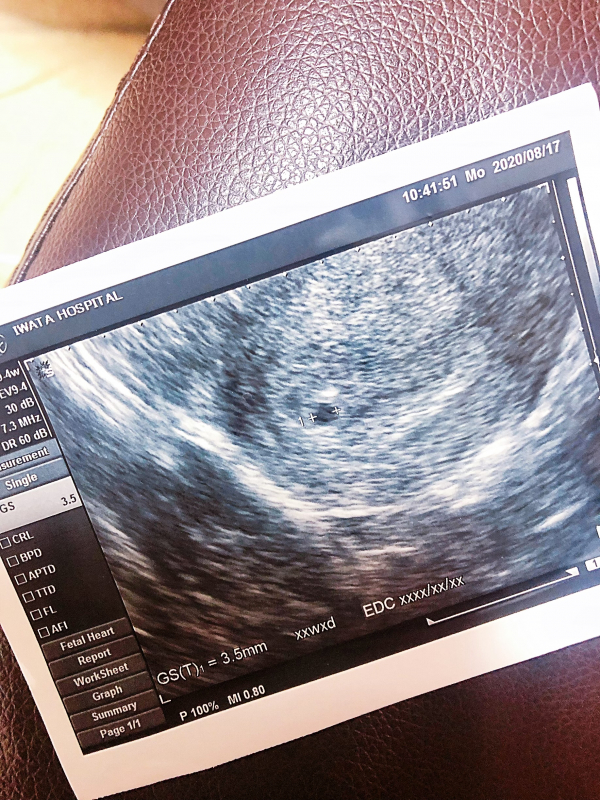

先生にみていただくと「これ胎嚢っていうの見える?大きさはまだ3mmくらいで小さいね」と言われ、こんなに小さいのに妊娠検査薬がくっきり反応出たり、軽い悪阻みたいな症状も出るんだとビックリしました。

エコーで赤ちゃんの袋も確認できたのですね。

まだはっきりと予定日も出ていないと思いますので、週数も出ていないかと思います。

排卵の時期などもわからないと思いますので、もう少し赤ちゃんの様子を見ながら予定日も見ていくことになるのではないかと思いますよ。

ご自身で計算をされて出てきた週数からすると赤ちゃんの袋は確かに小さめになるかもしれませんがはっきりとその週数とまだ決まってはいません。今確かにお腹の中に赤ちゃんはいてくれています。引き続きお腹の赤ちゃんにたくさん声をかけていただきながらお過ごしいただけたらと思います。